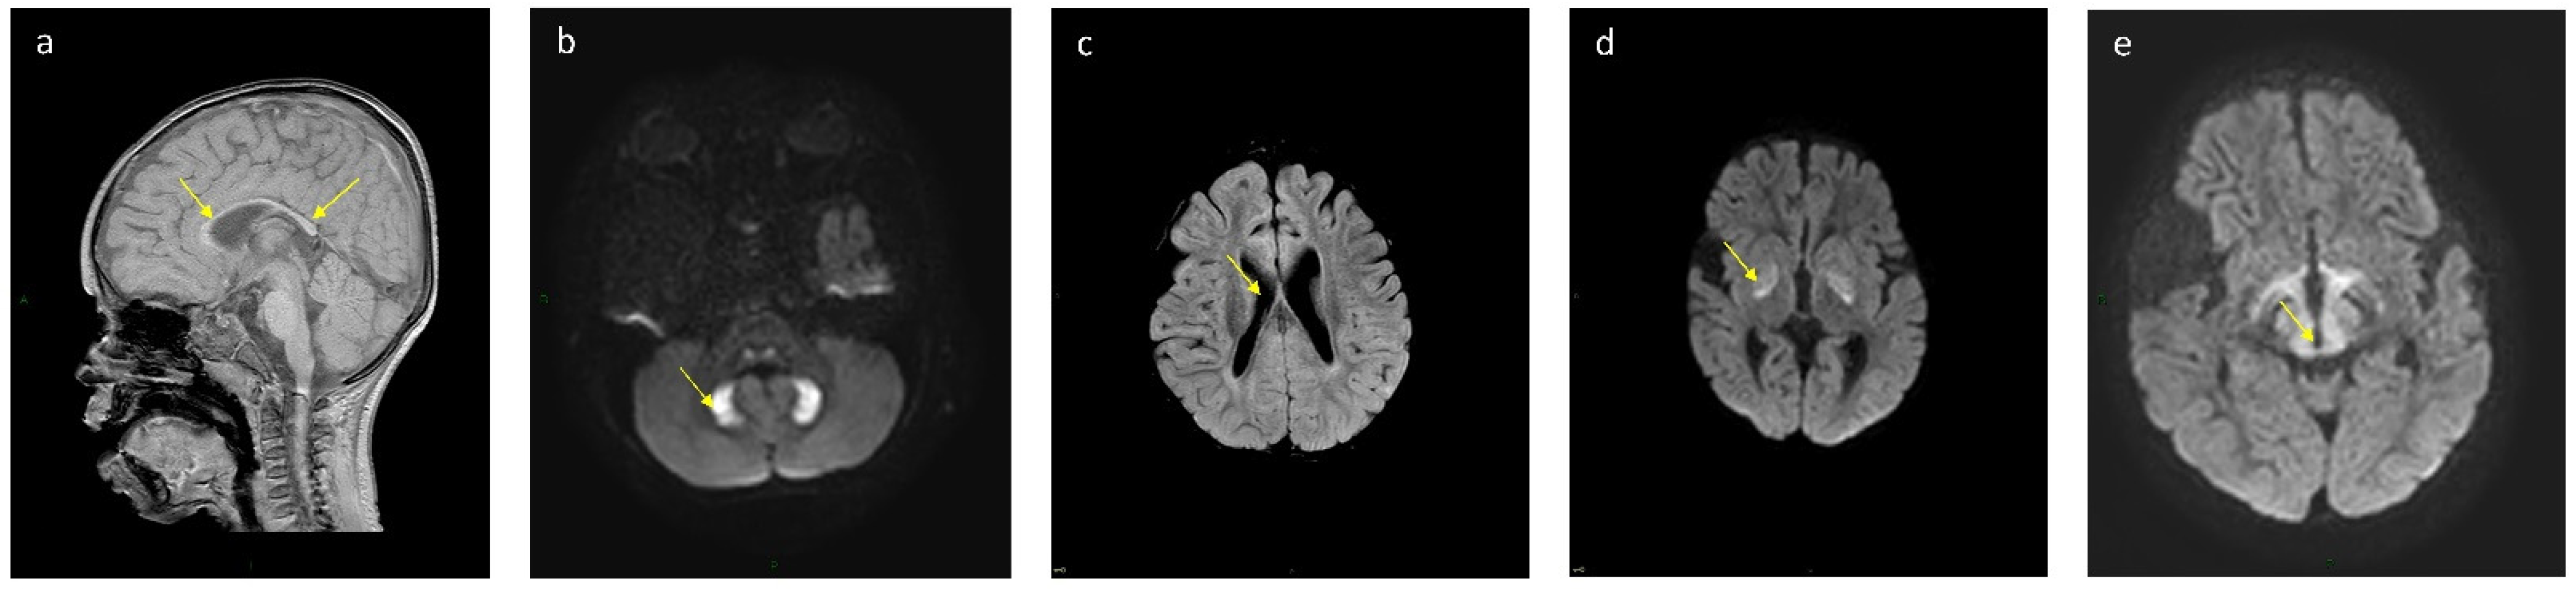

| Patient No. | Globus Pallidum | Dentate Nucleus | Corpus Callosum | Ventriculomegaly | Midbrain and Thalamus |

|---|---|---|---|---|---|

| k 16 | T2, Flair, DWI high signal, T1 low signal | Normal | Partial agenesis | Mild | Normal |

| 11 | T2, Flair, DWI high signal, T1 low signal | T2, Flair, DWI high signal, T1 low signal | Partial agenesis | No | Normal |

| k 12 | T2, Flair, DWI high signal, T1 low signal | Normal | Partial agenesis | Mild | Normal |

| 13 | T2, Flair, DWI high signal, T1 low signal | Normal | Partial agenesis | Moderate | Normal |

| k 6 | T2, Flair, DWI high signal, T1 low signal | Normal | Partial agenesis | Mild | Normal |

| k 7 | Normal | T2, Flair, DWI high signal, T1 low signal | Partial agenesis | Mild | T2, Flair, DWI high signal, T1 low signal |